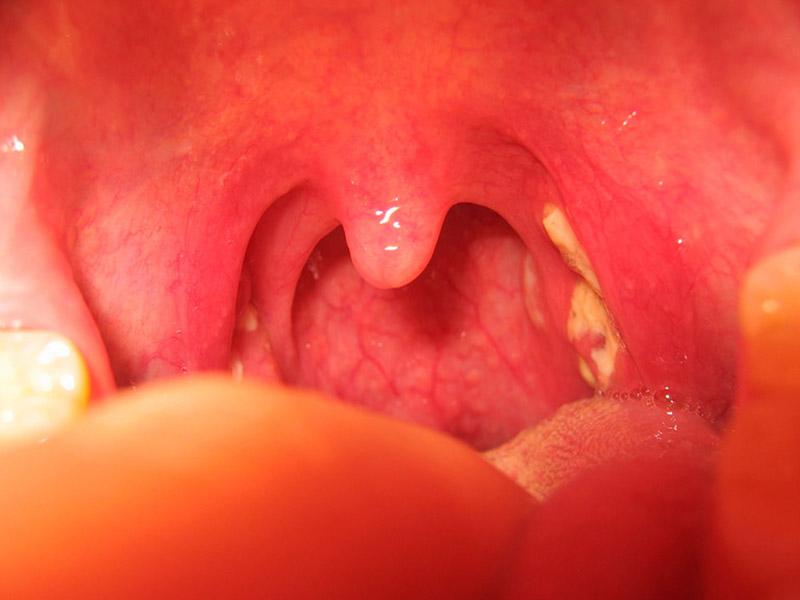

U vòm họng lành tính tiếp theo là viêm họng hạt, là một trong những dạng viêm họng mạn tính và hay gặp. Theo đó, viêm họng hạt thường chỉ phát hiện sau khi bệnh nhân mắc viêm họng hạt cấp.

Triệu chứng của viêm họng hạt thường bao gồm ngứa cổ, khó khăn khi nuốt thức ăn, vòm họng nổi các cục dưới dạng hạt li ti có màu đỏ hoặc màu hồng.

U nhú vòm họng là khối u vòm họng lành tính tồn tại dưới dạng khối sùi mềm, nhiều múi. Có thể bệnh nhân xuất hiện dấu các u này ở lưỡi gà hoặc ở amidan. Các triệu chứng mà u nhú vòm họng gây ra là ngứa cổ họng, vướng cổ họng làm ảnh hưởng tới việc ăn và nuốt thức ăn của người bệnh.

Hiện tượng viêm nhiễm kéo dài trong thời gian dài có thể khiến amidan trở nên to hơn so với cấu trúc bình thường, có thể có hốc với ranh giới rõ ràng. Triệu chứng của khối u vòm họng lành tính viêm amidan thường bao gồm ngủ ngáy, đục giọng, giọng nói ồm ồm, dễ mắc nghẹn, nôn và khó nuốt thức ăn.